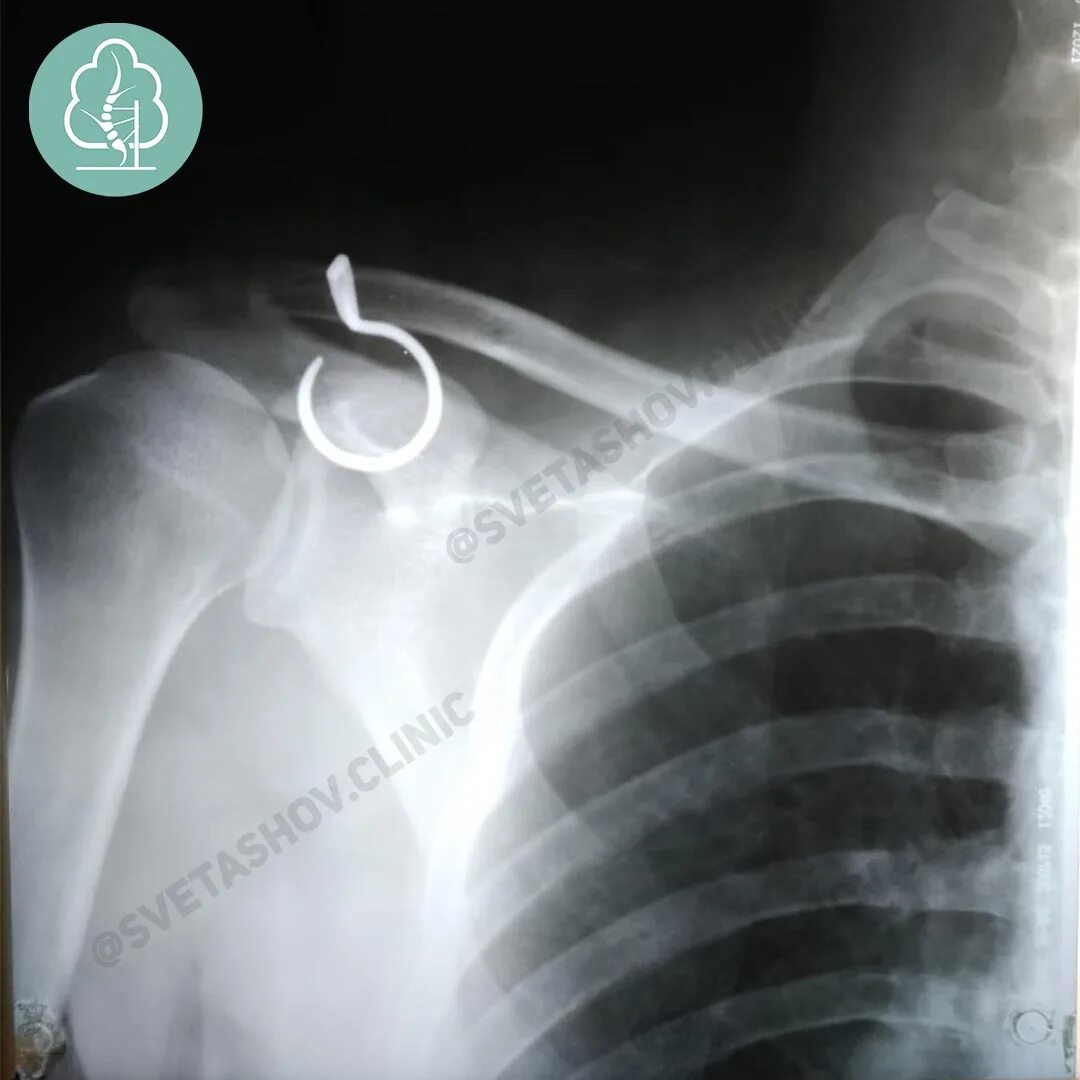

Вывих акромиально ключичного сочленения